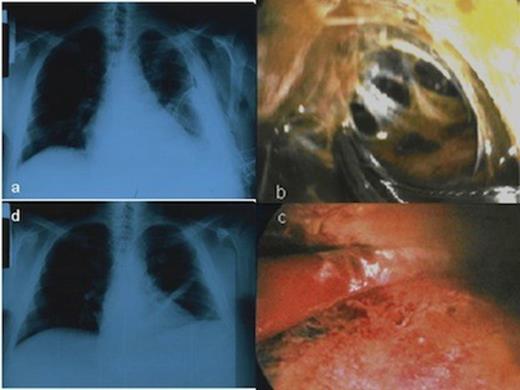

CXR showing the HH and the chest tube in the left hemithorax before the MT, b. Multiloculated thoracic empyema as a complication of HH, c. Disruption of fibrinous adhesions and debridement of parietal and visceral pleura, d. Chest X-ray following MT showed no recurrence of the hydrothorax

The patient was classified as Child-Pugh C category. Heart ultrasound was normal. We decided to perform talc pleurodesis by MT with local anesthesia in order to avoid potential hepatotoxic effects caused by drugs used in general anesthesia. Local anesthesia was performed with lidocaine and ropivacaine hydrochloride while midazolam, fentanyl citrate and propofol drips were used for sedation. The chest tube was removed and the thoracoscope entered the pleural cavity through a port. One additional incision (~1 cm) was made for instruments’ insertion. Surprisingly, inspection of the pleural cavity revealed multiloculated thoracic empyema. Fibrinous adhesions were disrupted and parietal and visceral pleura were debrided in order to unify the pleural space. The complicated pleural effusion was evacuated (Figure 1b, c). A segment from parietal pleura was sent for culture and pleural fluid was also sent for culture and biochemical analysis. Finally, talc pleurodesis was performed, so the lung parenchyma re-expanded with obliteration of the pleural cavity. Postoperatively, the patient had leukocytosis and fever. Pleural fluid was a transudate infected by Staphylococcus aureus sensitive to azithromycin which was administered to the patient. CXR following MT showed no recurrence of the hydrothorax (Figure 1d). Figure 2 shows the gradual improvement of patient's serum test levels during his hospital stay. The patient was discharged on the 8th postoperative day in good condition and did not have any recurrence in a follow-up of 4 months after the procedure.